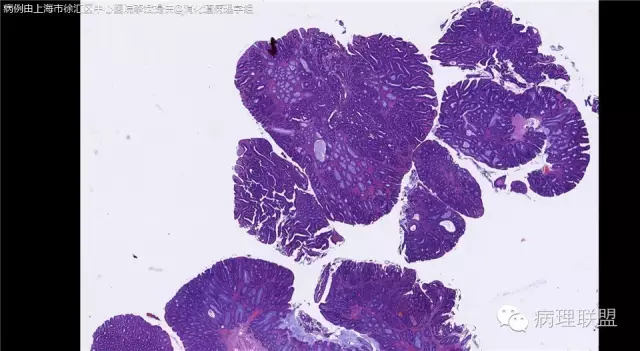

男,72岁,距肛门口30cm息肉。大体:灰白结节1.5*1*0.8cm拟发管状腺瘤并部分区高级别,请各位老师指导!(病例由上海市徐汇区中心医院 李斌 提供,致谢!)

这一例有两种不同看法,按WHO标准,为高级别,按实际工作,要发粘膜内癌。WHO第三版与第四版均提出,侵犯至粘膜下层才能诊断为癌,声称结直肠粘膜内没有淋巴管,发生转移的概率较小,但是粘膜内有血管,肿瘤侵出粘膜腺体基膜以外,就能侵犯血管,照样可以发生血道转移。文献报告与我们的工作实践,发现腺瘤、高级别(没有侵出基膜)的患者,同样有发生血道转移。因此,我们废弃了这一条WHO标准(不是所有的WHO标准都是一定要执行的)。只要异型增生腺体呈毛刺状、迷芽状侵出粘膜腺体基膜,位于粘膜肌层以内,就发粘膜内癌。

@李斌 结肠腺瘤这例我认为已经有黏膜下浸润了,因为有些腺体间的间质已经不是固有膜间质而是促结缔组织增生反应的间质了。但即使有浸润癌,如果息肉完整摘除、癌成分分化好、没有脉管瘤栓、浸润癌距切缘大于1mm(日本标准还要看浸润癌超出黏膜肌深度和肿瘤出芽情况),也不需要进一步治疗。所以,对于这类可能存在争议的病变,特别是息肉已经完整切除的病例,诊断的关注点就应该放在寻找需不需要进一步治疗的证据上了。@邓永键 2010版WHO在腺瘤部分的陈述中已经写出对于有局灶浸润性生长的病例也可以称黏膜内癌,他们在悄悄的让步。